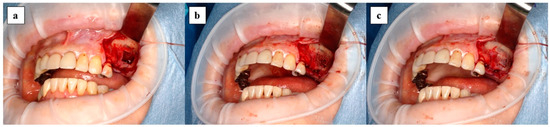

2.3. Preparation of the Complex of x3FD-PRP and Bone Graft Materials

The same amount of rehydrated FD-serum and 2% CaCl2 (Otsuka Pharmaceutical Factory, Tokushima, Japan) were mixed as the PRP activator. One unit of x3FD-PRP, which was prepared from 3 mL of PRP, was mixed with 1 g per 1 unit of either β-TCP granules (Cerasorb M; Curasan, NC, USA) or carbonate apatite granules (Cytrans Granules; GC Corporation, Tokyo, Japan) and was rehydrated with 1 ml of sterile purified water per 1 unit on the glass dish. This was then activated with 0.2 mL of PRP activator per 1 unit. After confirming gelatinization, the complex of x3FD-PRP and the β-TCP granules were transplanted immediately. A sterility test was performed in part of the x3FD-PRP which was used for transplantation. Figure 2 shows the preparation process for the complex of x3FD-PRP and bone grafting materials.

Figure 2. The preparation process for the complex of x3FD-PRP and bone grafting materials is shown: (a) FD-PRP powder and white particulate bone grafting materials; (b) complex of gelated x3FD-PRP and bone grafting materials; (c) given good operability.

The benefit of FD-PRP is that it is easy to store as its powder form enables storage in a refrigerator or even at room temperature: this characteristic facilitates the mixture with artificial bone [6]. Furthermore, this characteristic makes it possible to prepare a higher concentration of FD-PRP. Although x3FD-PRP was used in this study in accordance with our previous study, FD-PRP with an increased concentration rate may be effective for bone regeneration. Further studies are necessary to determine the most suitable concentration rate of FD-PRP. There are other advantages such as good operability and an ease of maintenance at the local site because the PRP gelates with the bone grafting materials (Figure 2). It would be useful when perforation occurs in the maxillary sinus mucous membrane.